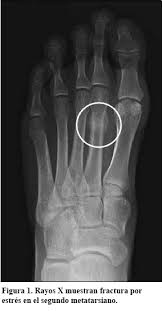

La fracturas por estrés son aquellas fisuras que se producen en el hueso debido a una excesiva actividad de manera continuada y repetitiva. Frecuente en deportistas y se localiza en los metatarsianos, sobretodo en el 2º y en 5º metatarsianos.

El diagnóstico por imagen es de elección para llegar a un diagnóstico, Rx, resonancia, tac